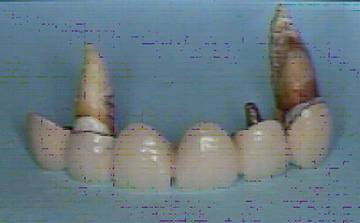

上の写真はエンドとペリオの治療が不完全なために根尖病巣ができたり骨の吸収がある状態。

下が抜歯になった歯(ブリッジ)